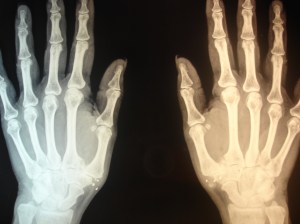

Uno de los procesos que mejor evolucionan tras la colocación de implantes de oro periarticulares es la rizartrosis del pulgar. Puede que al no ser una articulación de carga la respuesta al tratamiento sea más rápida. La degeneración articular con la pérdida de la congruencia anatómica no es un obstáculo para la recuperación funcional; la mejoría de la movilidad y la fuerza de prensión digital son notables en los casos tratados, así como la disminución-supresión del dolor. Parece cada día más evidente el relevante papel de los tejidos blandos articulares y periarticulares en la morbilidad  articular. Uno de los efectos biomédicos descritos en experimentación animal es la competencia local del oro con el calcio que se observa en las exóstosis y calcificaciones periarticulares. Se aprecia en las siguientes RX el caso de una paciente con rizartrosis de pulgar bilateral que requería una ingesta diaria de diclofenaco durante 12 años, que suspendió al día siguiente de la intervención hace unos 4 meses. Puede verse un cambio significativo en la calcificación de la mano izquierda. Es uno de los casos (bilateral) en el que el resultado funcional (movilidad y fuerza).

aspecto antes de la RX con las calcificaciones